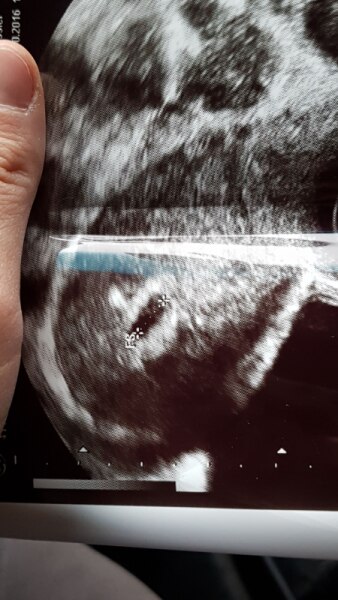

Huhu meine lieben.. Ich wa gestern im kh gewesen wegen meiner negativ test rei. Auf jeden Fall hat sie mich da untersucht und im Ultraschall genau wie Freitag die fruchthöhle gesehen. Ansonsten keine Auffälligkeiten. Kein Blut. Nichts... Der Fa am Freitag sagte ich wäre 4+4 anhand der grösse der fruchthöhle (habe ja noch keinen zyklus gehabt ) Auf jeden Fall machte sie dann gegen 16 Uhr auch einen urin test der dort wie erwartet negativ aus fiel (mich können zu hause ja nicht 1000 Tests verarschen) Und erklärte mir dann was von inaktiver ss und abort ... Mich macht das völlig verrückt. Ich fühle irgendwie das das nicht stimmt. Aber die Tests. Auf jeden wollte ich das sie Blut abnimmt und sagte ich soll am Dienstag so lang keine blutung kommt zu meinem fa. Sie ist der Meinung bei der grösse der fruchthöhle müsste der test definitiv positiv sein und Blut wäre nicht nötig. Jetzt geh ich hier kaputt... :( Hatte einer einen ähnlichen Fall.? Ich brauche nervlich inputt. Hänge euch nen bild das der Fa mir am Freitag mitgegeben hat an Liebe grüsse

Bild zu Kh befund evtl abort... :( tot traurig aber verunsichert - Schwanger - wer noch? Rund um die Schwangerschaft